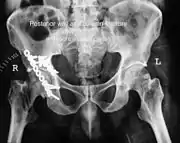

X-ray of T shape fracture